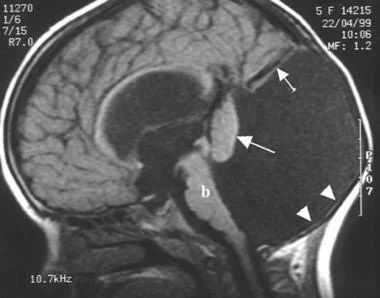

Картина нейросонографии в первые сутки жизни: в задней черепной ямке при коронарных и сагиттальном сканированиях наблюдается крупное анэхогенное («кистовидное») образование, включающее расширенные III и IV желудочек; полушария мозжечка резко уменьшены, червь не определяется; мозжечковый намет смещен вверх.

В динамике по данным НСГ выявлена перивентрикулярная ишемия, подтверждён синдром Денди-Уокера, вентрикуломегалия (как часть симптомокомплекса) и повышенная резистентность сосудов мозга.

- МРТ головного мозга. Магнитно-резонансная томография в сагиттальной и аксиллярной проекции демонстрирует расширение четвертого желудочка, грубые нарушения развития мозжечка, другие структурные аномалии.